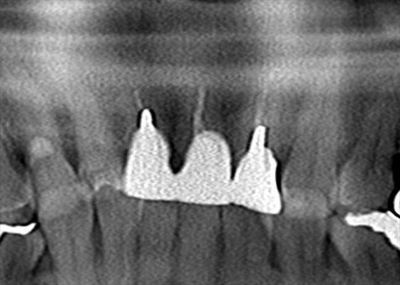

CT_20200407202958_R27.jpg

初診時のレントゲン写真です。

前歯3本は過去に神経を取ってある歯です。